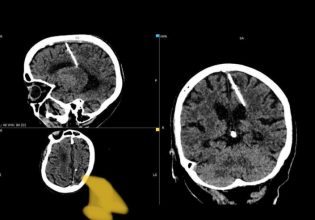

Οι γιατροί λοιπόν αποφάσισαν να απενεργοποιήσουν το μη λειτουργικό τμήμα του εγκεφάλου της, περνώντας από το φυσικό άνοιγμα του εγκεφάλου που ονομάζεται Sylvian fissure, δήλωσε ο Aaron Robison.

Ουσιαστικά ο Robison αποσύνδεσε την αριστερή πλευρά του εγκεφάλου της Brianna, η οποία επιτρέπει στη δεξιά πλευρά να πάρει τον έλεγχο και να ανακτήσει τη λειτουργικότητα του σώματος.